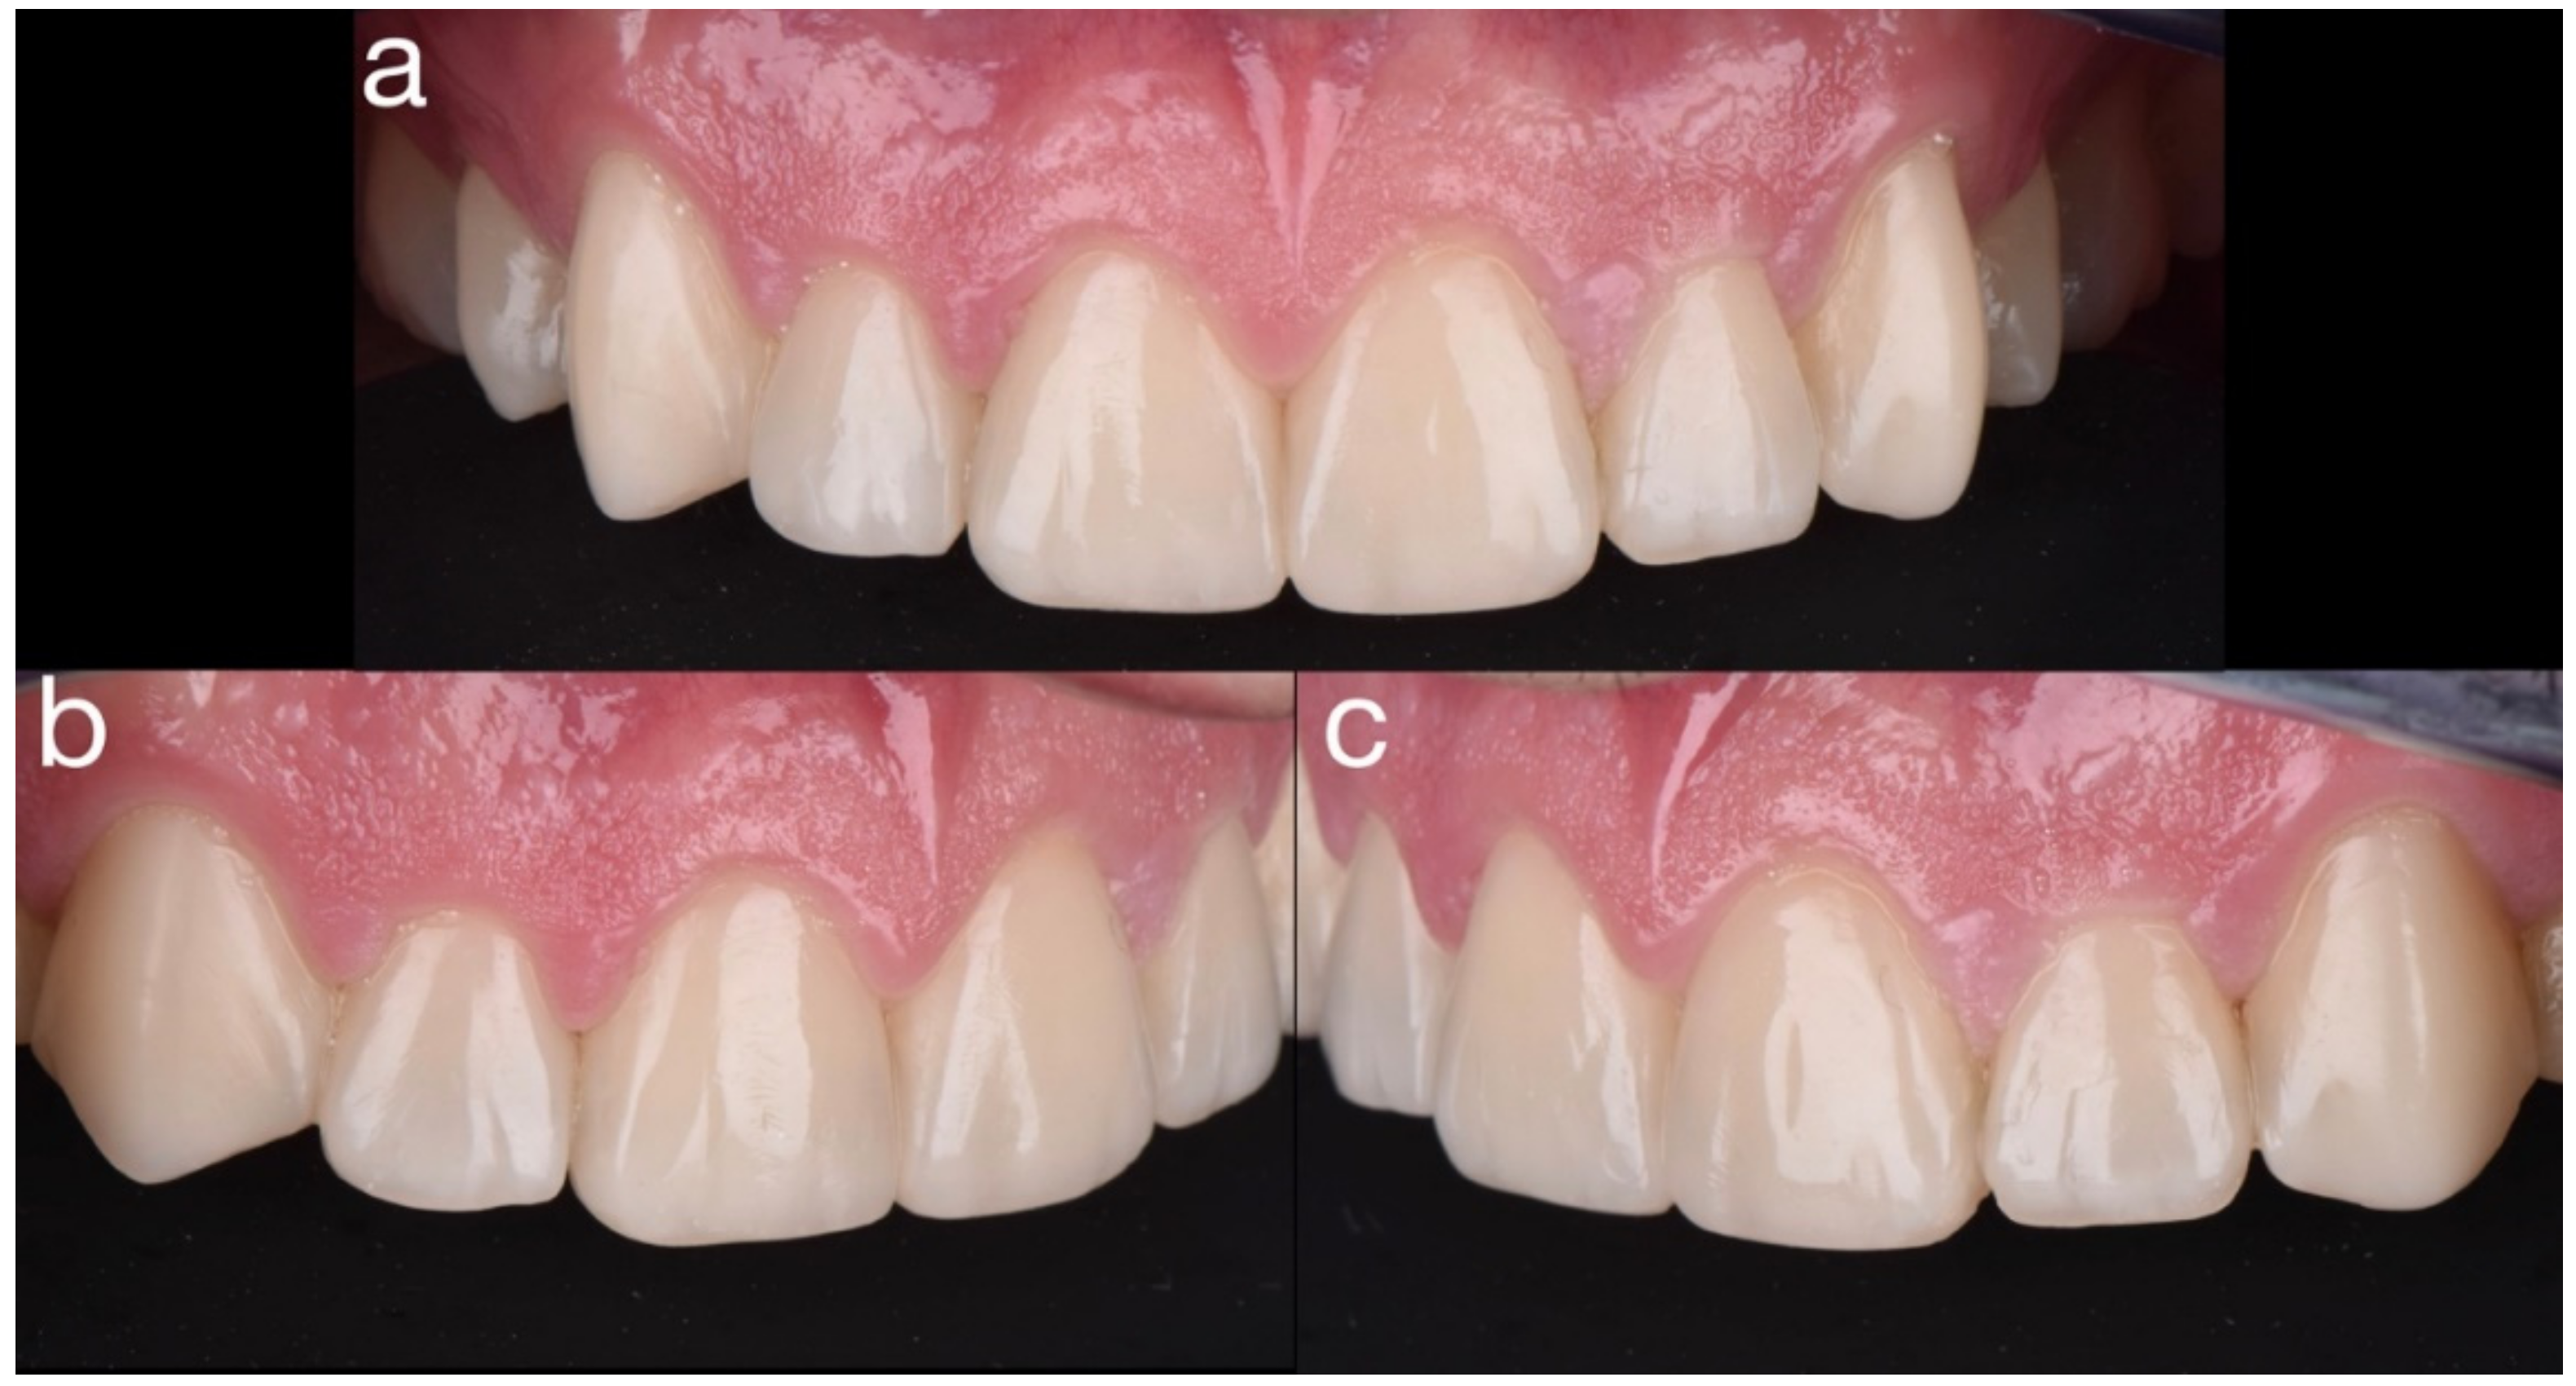

2.2. Restorative Phase

3. Discussion